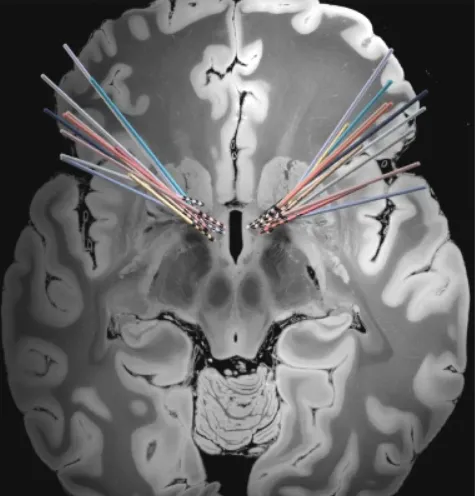

就像起搏器设备如何调节心脏的电活动一样,DBS设备调节大脑的电活动。DBS设备将来自发生器的电脉冲通过一对细导线(导线)传输到大脑的特定目标区域,这些脉冲通常被植入胸腔上部。通过精确调整刺激参数,电脉冲能够促使功能失调的大脑回路逐渐恢复至正常状态。

该团队的目标是了解在theta(4—8赫兹)到alpha(8—12赫兹)范围内的低频大脑震荡是如何在患有严重的,治疗难治性强迫症的个体中发生改变的。大量科学文献发现,theta(4—8赫兹)到alpha(8—12赫兹)范围内的低频大脑震荡在认知过程中发挥着突出作用。为了做到这一点,他们利用了现代DBS设备的一个新功能——不仅能够提供刺激,还能记录大脑活动。

在植入DBS系统后开始录音。由于刺激通常在几天到几周后开始,研究小组能够测量严重症状状态下的神经活动模式。有趣的是,他们发现9赫兹(θ - α边界)腹侧纹状体神经活动表现出明显的昼夜节律,在24小时的周期内波动。